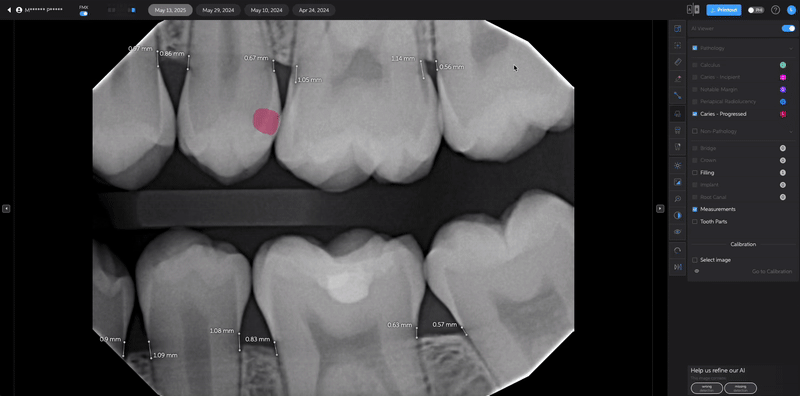

Editing Bone Measurements

In addition to adjusting detections, you can also edit bone measurements to achieve a more precise analysis of periodontal health:

- Select the Bone Measurement Edit Tool.

- Adjust measurement points to better reflect actual bone levels observed on the radiograph.